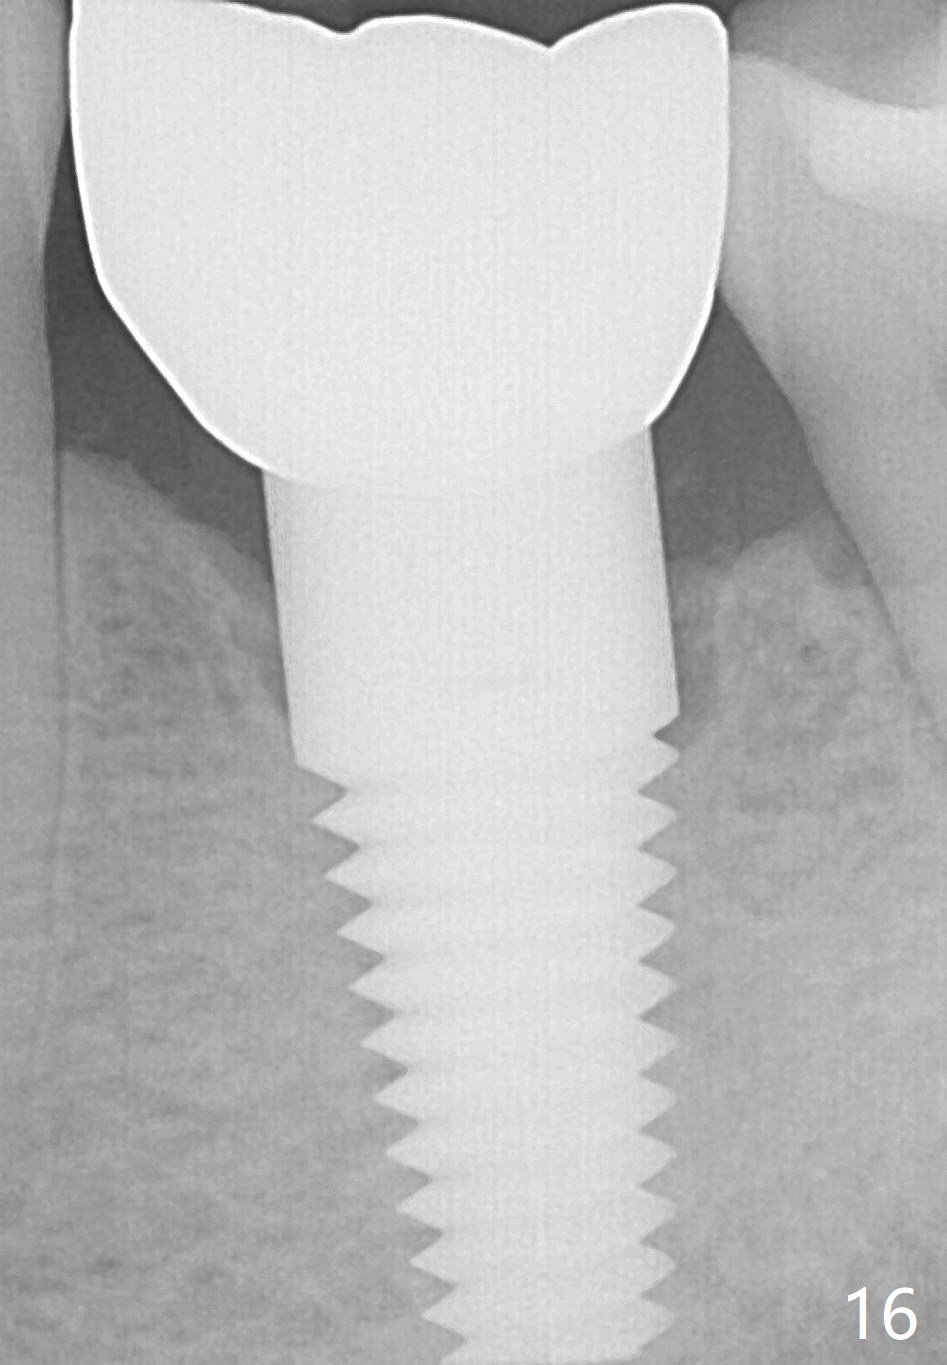

Two and a half months post cementation, the buccal metal show is much less and confined to the midbuccal portion. It appears that the papillae increase their mesiodistal dimension (data not shown). Bone appears to remain stable over the implant surface 2.5 and 9 months post cementation (Fig.12 >,13). The papillae around the implant crown remain normal 11 months post cementation (Fig.14 *). No bone loss is noticed 26 (Fig.15) or 38 (Fig.16) months post cementation. There is no bone loss around the 7x17 mm tissue-level implant 6 years 8 months post cementation (Fig.17).